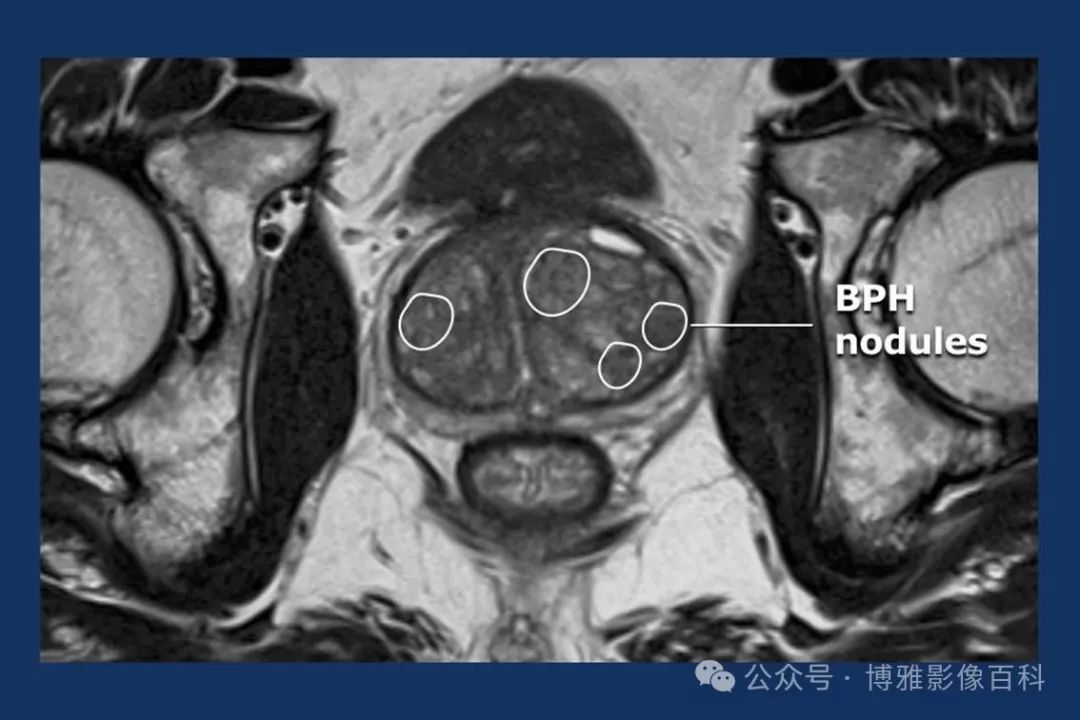

前列腺良性增生患者的轴向T2 图像,其他方面正常。外周带是一薄层均匀的高信号,边界清晰连续性的低信号包膜。移行带通常表现为不均匀中等信号,病灶被边界清楚的BPH良性前列腺增生结节所取代。精囊具有均匀T2高信号。未见淋巴结肿大。